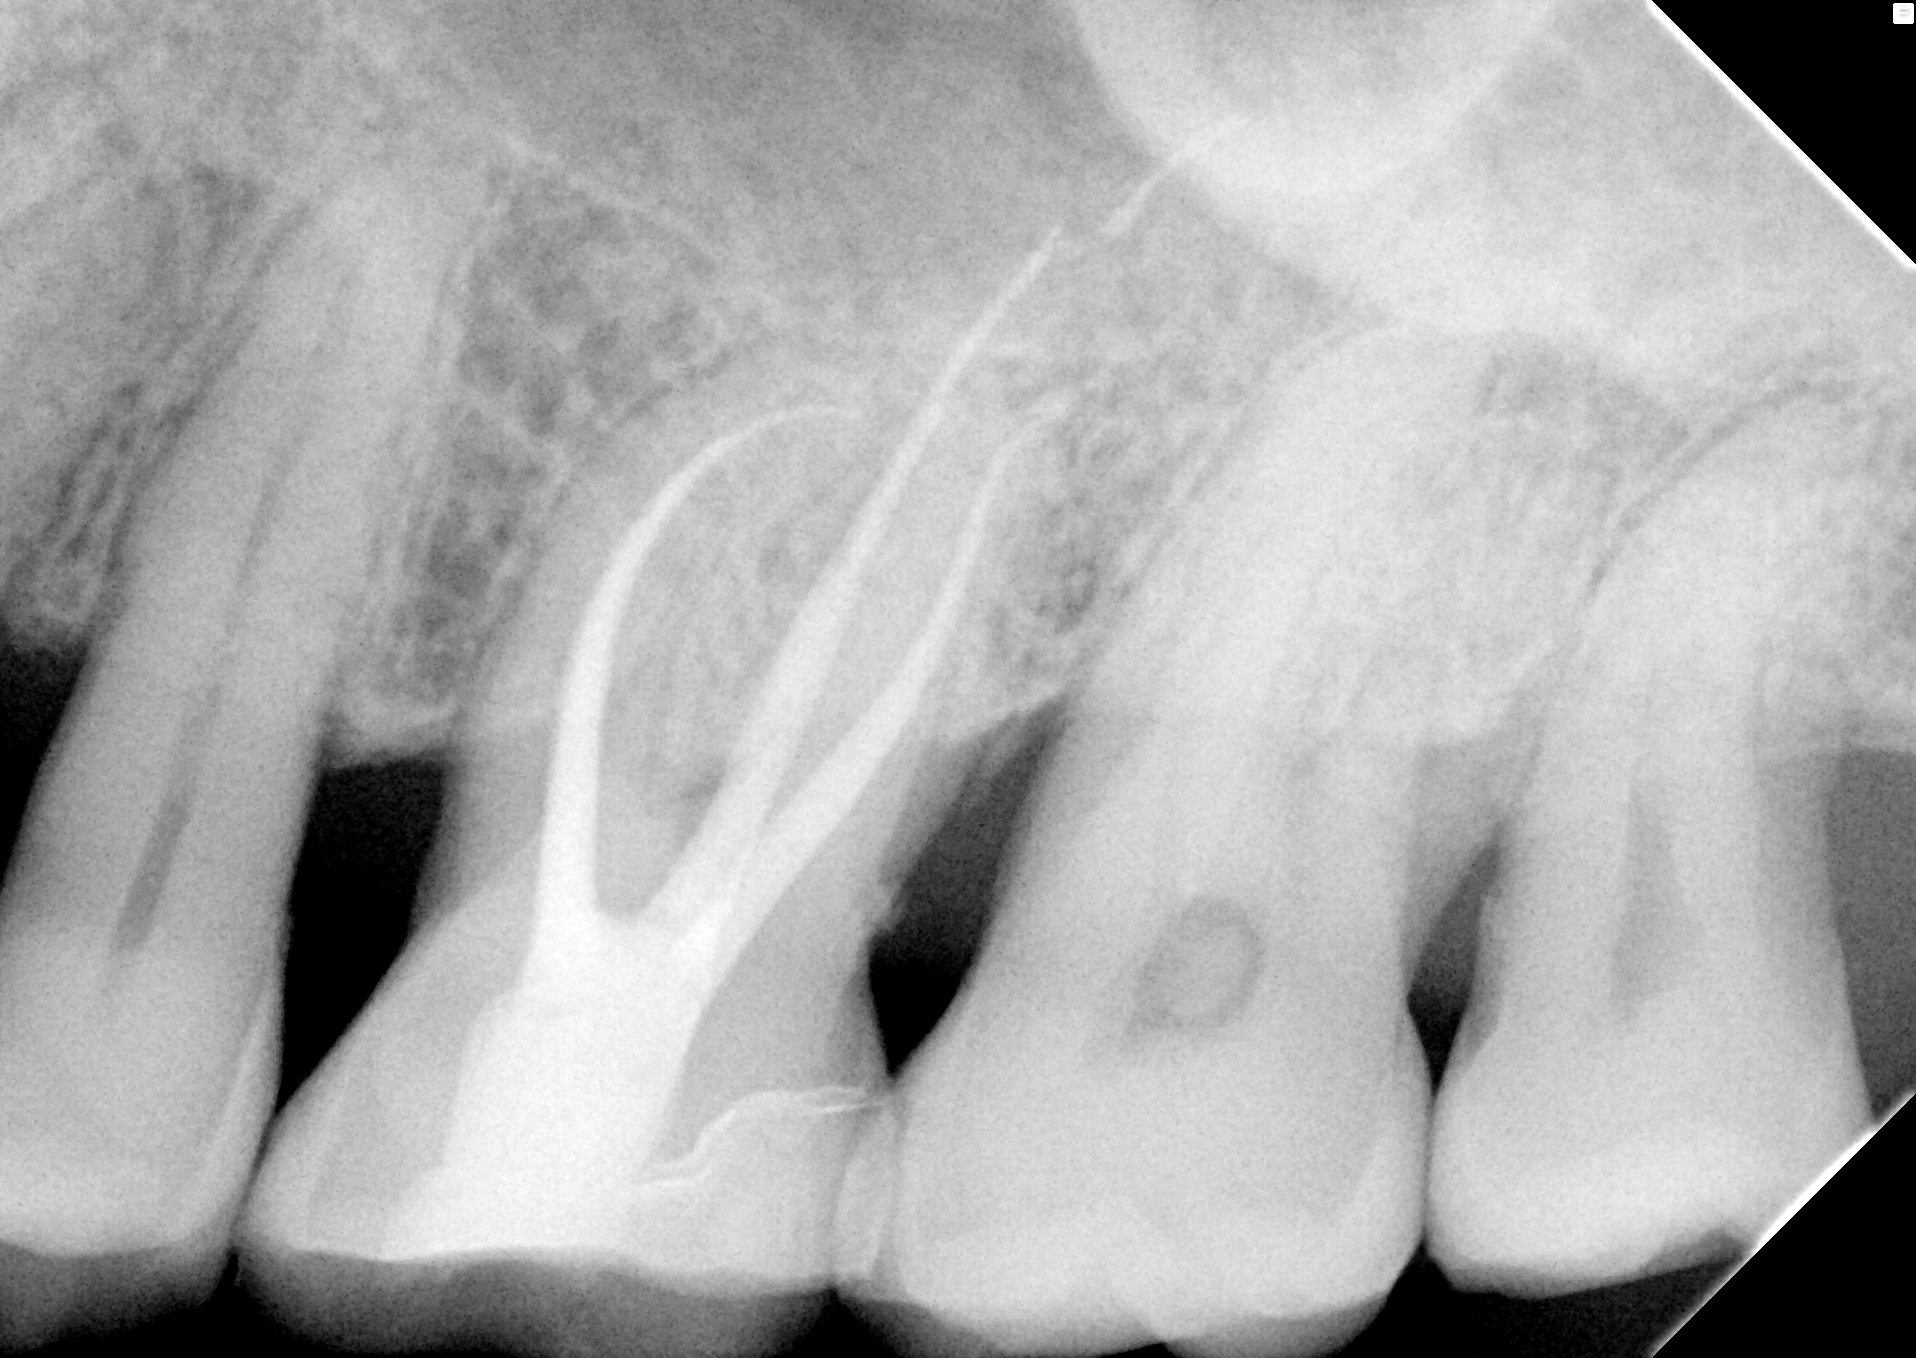

Der Patient stellte sich mit einer Aufbissempfindlichkeit an Zahn 26 vor. Der Sensibilitätstest mit Kälte war negativ. Perkussion war schmerzhaft. Klinisch zeigte sich eine schräge komplizierte Kronenfraktur bei avitaler Pulpa. Wir haben unter Kofferdam, mit dem OPMI Zeiss ProErgo, ProTaper next … die Wurzelkanalbehandlung durchgeführt und abgeschlossen. MB2 ist von MB1 überlagert, wurde aber aufbereitet und gefüllt.